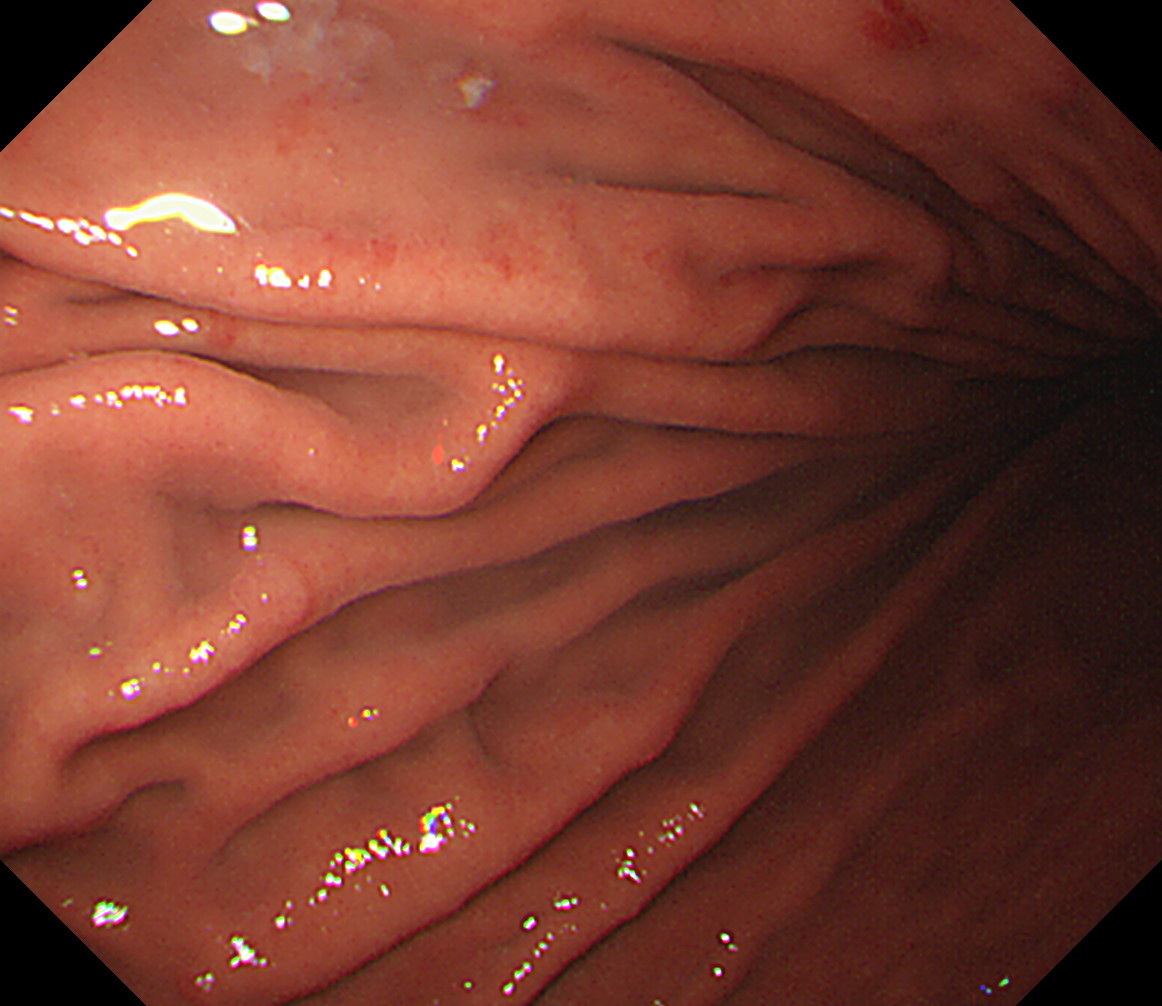

14 体下部小弯(角上部) [J反転]して以降見上げです 体下部小弯(角上部)

15 体中部小弯 接線になり見逃しやすい部位です 体中部小弯

16 体上部小弯 接線になり見逃しやすい部位です 体上部小弯